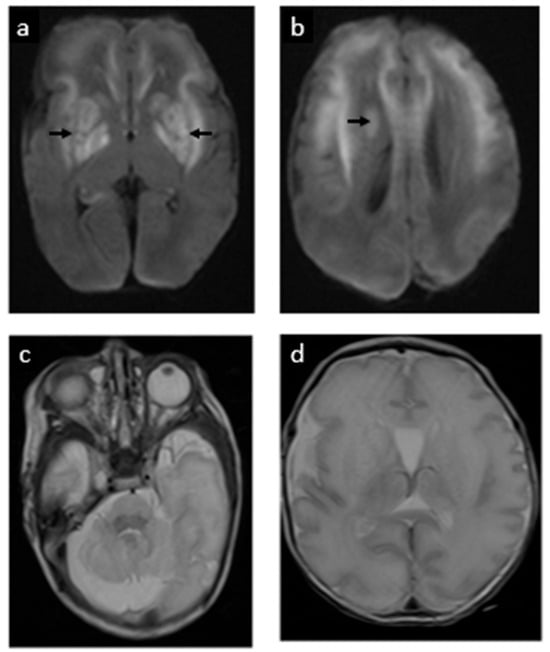

| 1 | Hitzert et al., 2012 [20] | Yes | None reported | Day 0 (4 h after birth) | 36 w 3 d | Brief neonatal seizures; mildly delayed cognitive, rest normal neurodevelopment at follow-up (21 months) |

| 4 | Schwahn et al., 2015 (Patient 5) [16] | Yes (older sib; prenatal) | None reported (dysmorphic features at birth) | Day 0 | ~36 w | Seizure-free, normal development by age 3 years |

| 6 | Schwahn et al., 2015 (Patient 7) [16] | Yes (older sib; prenatal) | None reported (dysmorphic features at birth) | Day 0 | 40 w | Seizure-free, near-normal development long-term by age 2 years |

| 16 | Etchegaray et al., 2025 (this case) | Yes (16 w via amniocentesis) | Fetal MRI normal at 22 w; mega cisterna magna at 28 w | Day 0 (within 10 min of birth) | 32 w 6 d | Neonatal seizures (resolved by 60 h); discharged D37. Developed dystonic quadriplegic CP by 6 mo (cognition relatively spared); remains seizure-free at 24 mo |